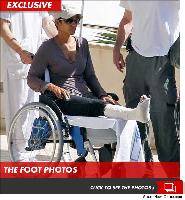

В случае перелома шейки бедра компания МосРентген Центр госпитализирует в Склиф для эндопротезирования.